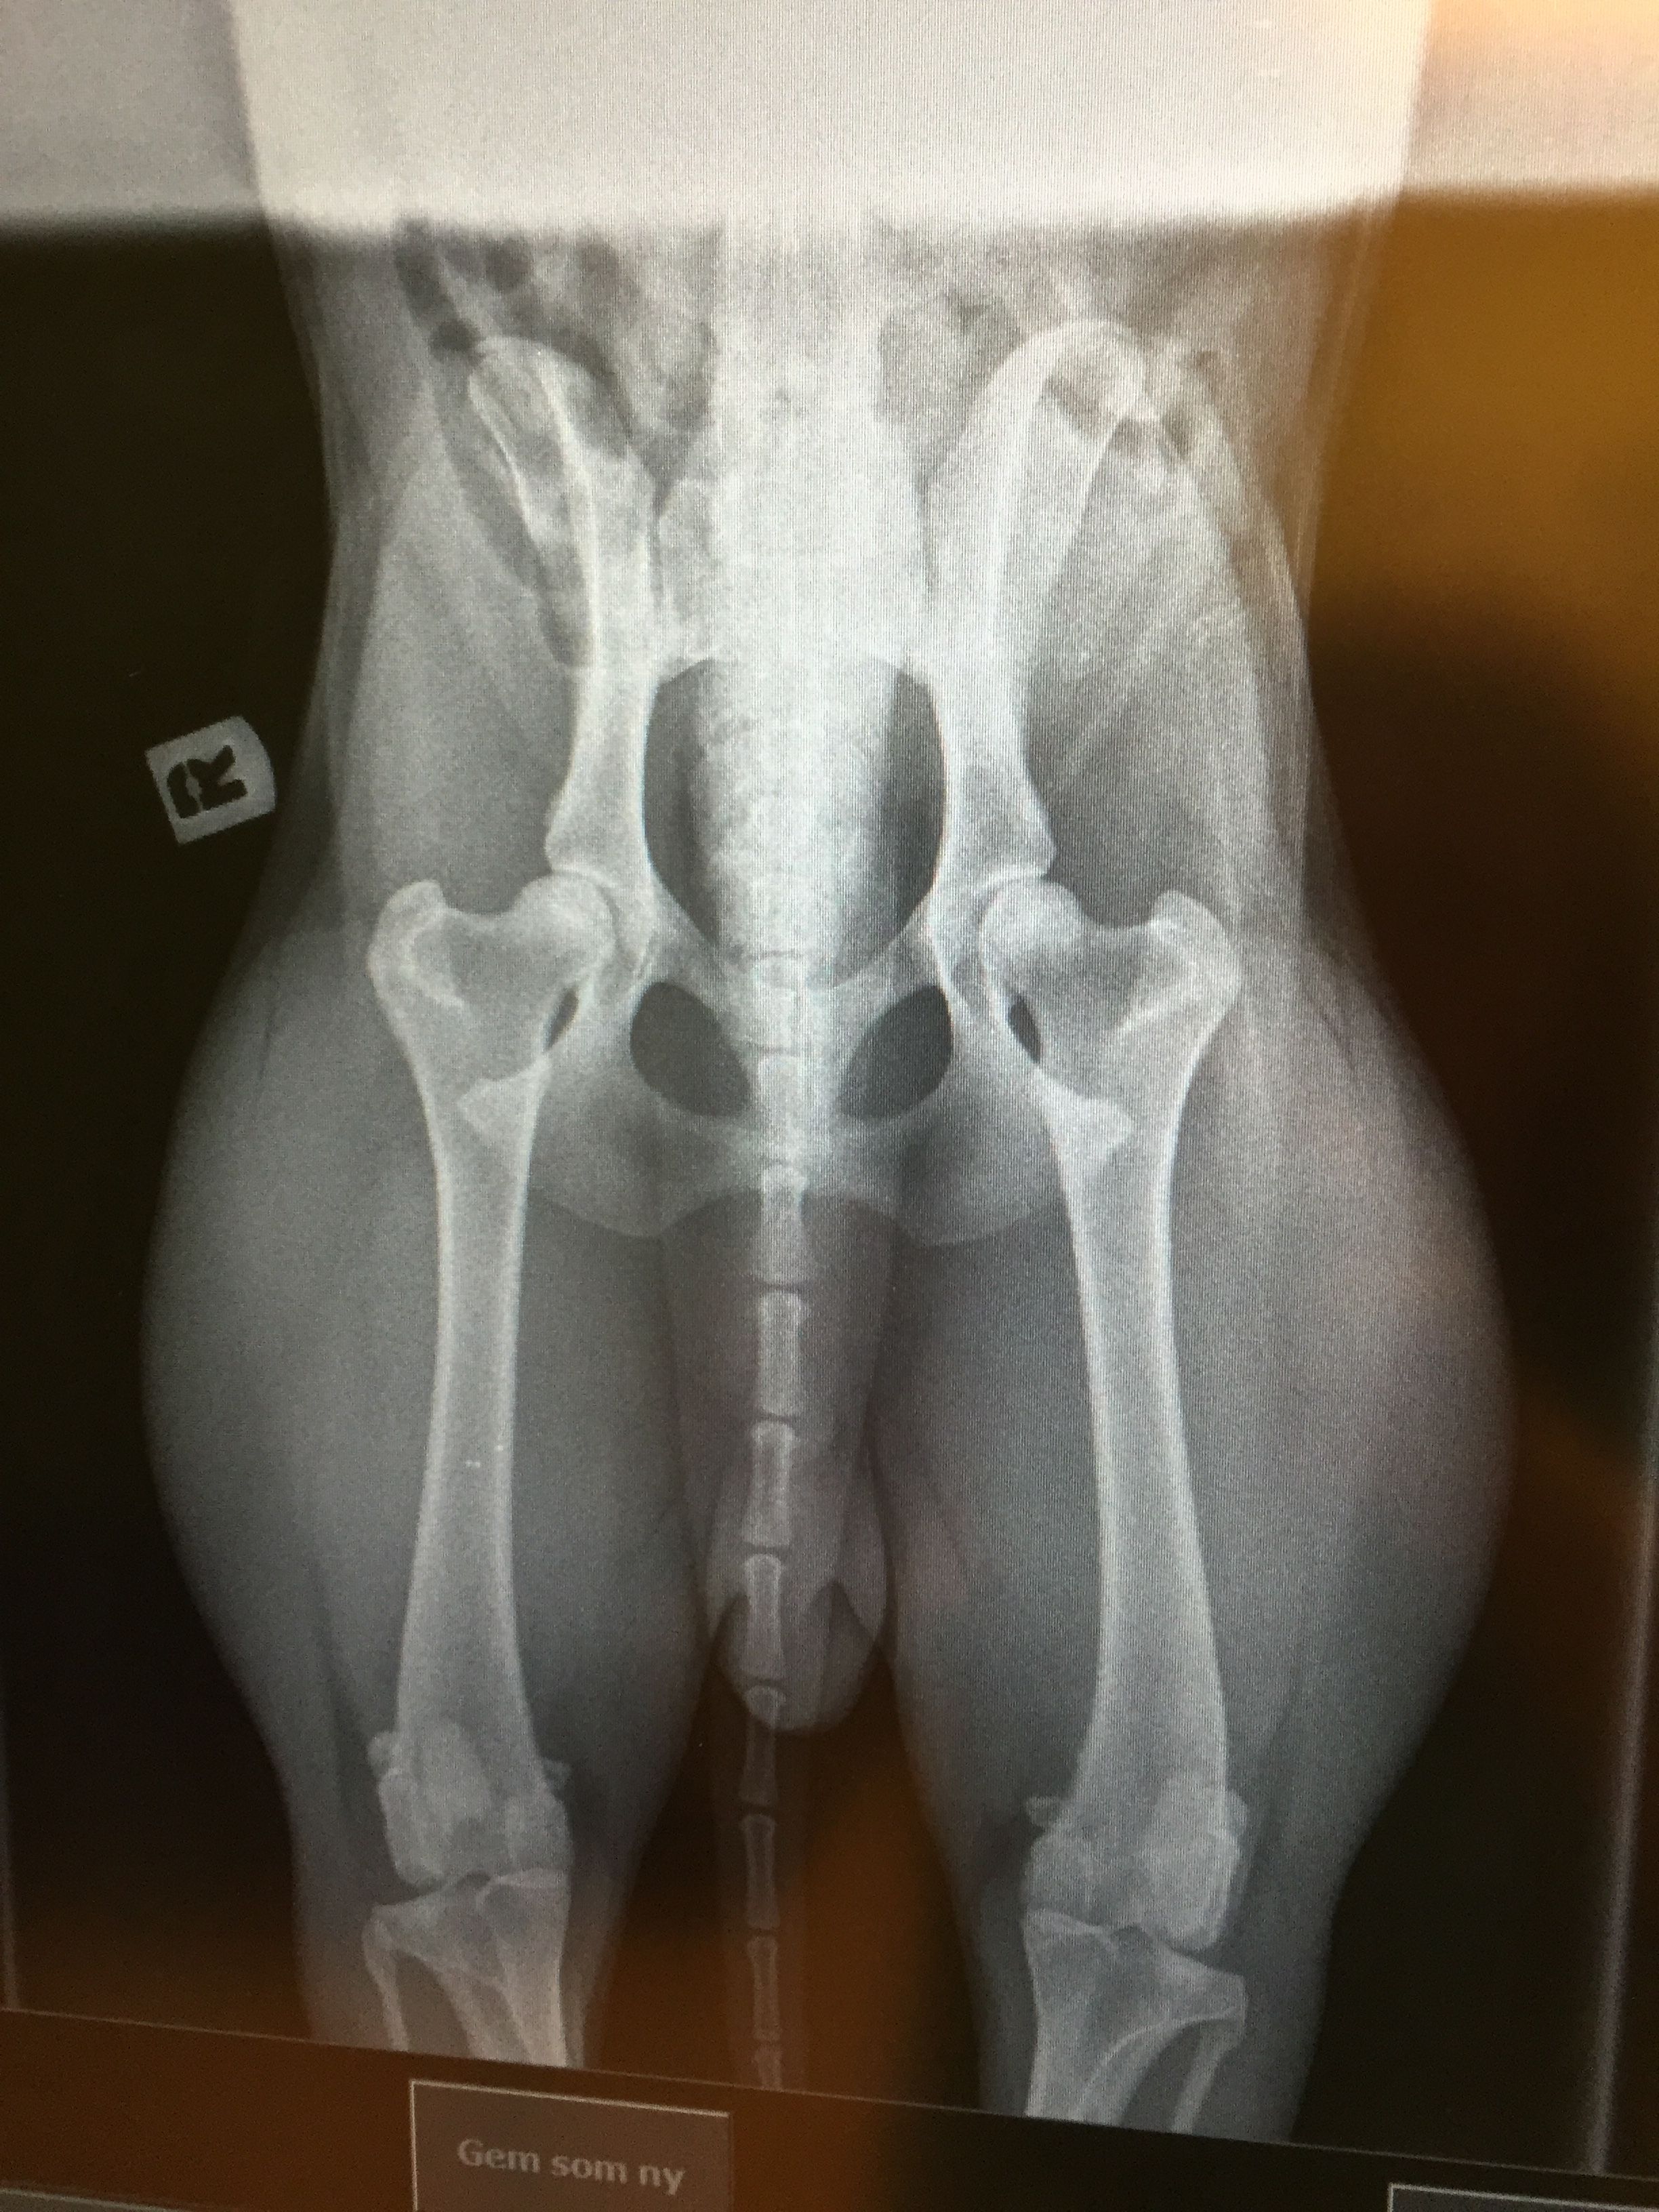

Hunden bedøves let, lægges på ryggen med benene strakt helt ud, og der tages et røntgenbillede af dens hofteled i denne position.

Hunden bedøves let, og der tages i alt 3 billeder af dens hofteled:

Et standard HD-billede som ovenfor beskrevet, et kompressions-billede hvor hofteleddet trykkes sammen, samt et distraktions-billede, hvor hofteleddet udsættes for et let press.